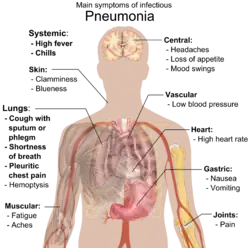

Клиническая картина

«Типичная» пневмония характеризуется резким подъёмом температуры, кашлем с обильным выделением гнойной мокроты и, в некоторых случаях, плевральной боли. При исследовании: укорочение перкуторного звука, жёсткое дыхание, усиленная бронхофония, усиленное голосовое дрожание, сначала сухие, а затем влажные, крепитирующие хрипы, затемнение на рентгенограмме. Такую пневмонию вызывают Streptococcus pneumoniae, Haemophilus influenzae, Escherichia coli, Klebsiella pneumoniae.

«Атипичная» пневмония характеризуется постепенным началом, сухим, непродуктивным кашлем, преобладанием в клинической картине второстепенных симптомов — головной боли, миалгии, боли и першения в горле, слабости и недомогания при минимальных изменениях на рентгенограмме. Этот тип пневмонии вызывают, как правило, Mycoplasma pneumoniae (микоплазменная пневмония), Legionella pneumophila (легионеллёзная пневмония), Chlamydia pneumoniae (хламидийная пневмония), Pneumocystis jirovecii (пневмоцистная пневмония).

«Вторичная»: аспирационная, септическая, на фоне иммунодефицита, гипостатическая, посттравматическая и другие.

Серьёзными осложнениями пневмонии могут являться: абсцесс и гангрена лёгкого, плеврит, эмпиема плевры, обструкция, острая дыхательная недостаточность, эндокардит, перикардит, менингит, отёк лёгких, сепсис.